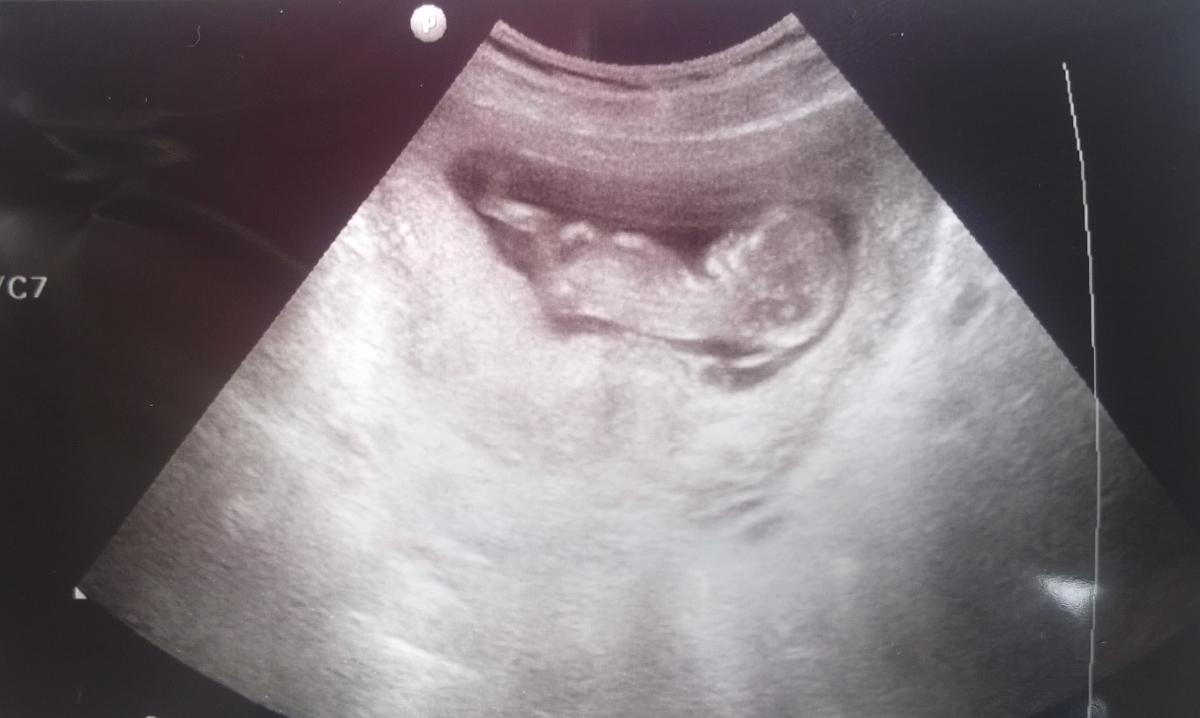

@lolo8280: Nagyon szép kis formás. Nem látszik még, hogy kettő baba lenne

Köszönjük a fotót ![]()